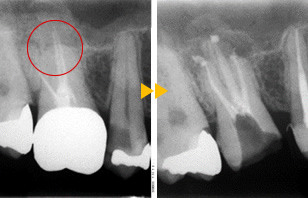

感染根管治療

感染根管治療(やり直しの処置)リトリートメント

リスクや副作用について

• 術後の痛み、違和感、穿孔、歯根破折、器具の破折がおこる場合があります。

• やり直しの治療は成功率は低く、これを何度か繰り返すと、歯が薄くなり保存不可能になってしまう場合があります。再治療、外科処置、抜歯などの処置が必要となる場合もあります。